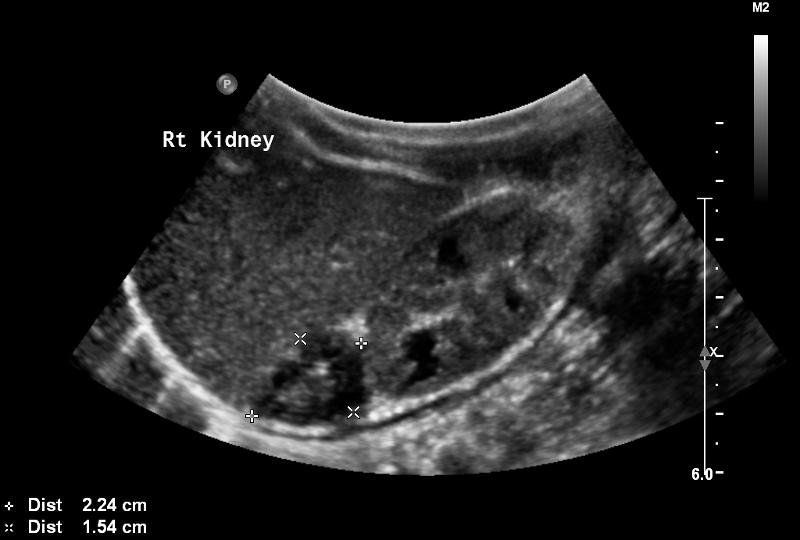

3 years

large asymptomatic flank amss

hypertension

fever

hematuria

Wilm's Tumor

3 years

90% survival